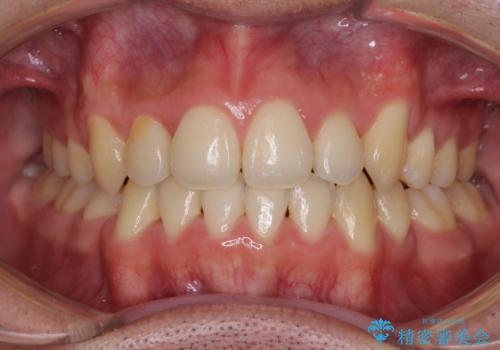

前歯のデコボコを短期間で解消 ワイヤー装置による抜歯矯正

- 上下前歯のデコボコを気にして来院された患者様です。

デコボコが強いため、非抜歯で矯正をすると出っ歯仕上がりとなるため、上下左右の第一小臼歯4本を抜歯することとしました。

当初予定は2年半程度と伝えていましたが、2年にも満たない期間で治療を終えることができました。